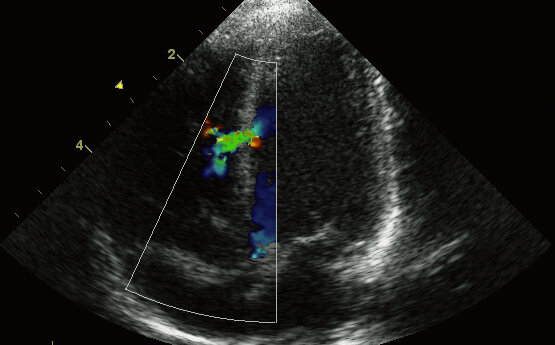

Описание узи

Через некоторое время было повторное узи, чтобы посмотреть сердечко малыша.

Снова повторился диагноз ДМЖП. Но как мне объяснила гинеколог, «он (видимо, дефект) уменьшается», а это хорошая тенденция.

Во время третьего скрининга на 34-ой неделе, этот показатель ещё уменьшился, но пока аббревиатура ДМЖП еще стояла в протоколе узи.